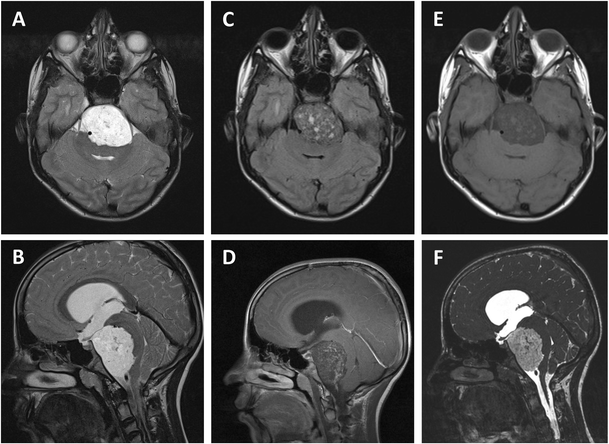

Preoperative MR images. a, b Axial and parasagittal T2-weighted MRI scans showing an inhomogeneous hyperintense prepontine lesion with a mass effect on the brainstem. c, d Axial and parasagittal T1-weighted MRI scan after administration of gadolinium contrast show inhomogeneous enhancement. e Axial T1-weighted MRI scan shows an inhomogeneous hypointense prepontine lesion. f Parasagittal constructive interference steady state (CISS) MRI scan shows an inhomogeneous hyperintense prepontine lesion